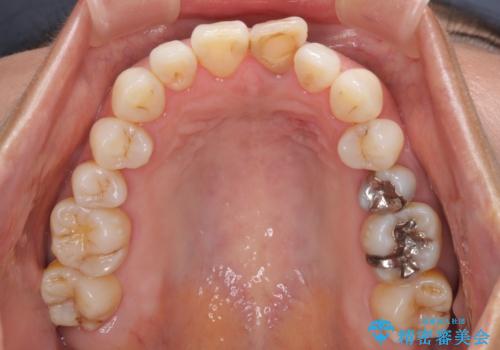

- 10年以上前に神経を取り除いた前歯の変色が気になるとのことで来院された患者様です。

レントゲン写真より、歯根の炎症が認められなかったため、ファイバーコアによる土台築製後、オールセラミッククラウンにて補綴することとしました。